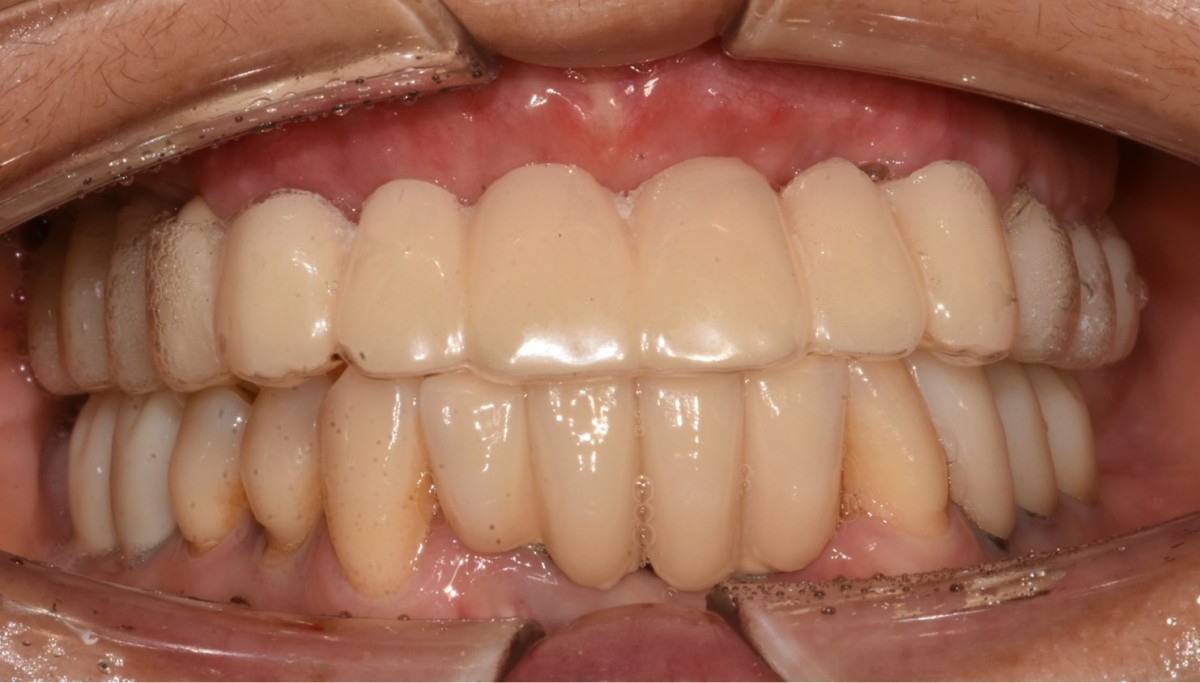

A 46-year-old female patient didn’t

have any systemic problems but a poor oral condition.

The patient is scheduled

for the implant and general prosthetic restoration in various parts. First of

all, the vertical stop is completed by several prostheses in the posterior

region, and the final stage of intraoral restoration is to proceed with an

anterior implant installation.